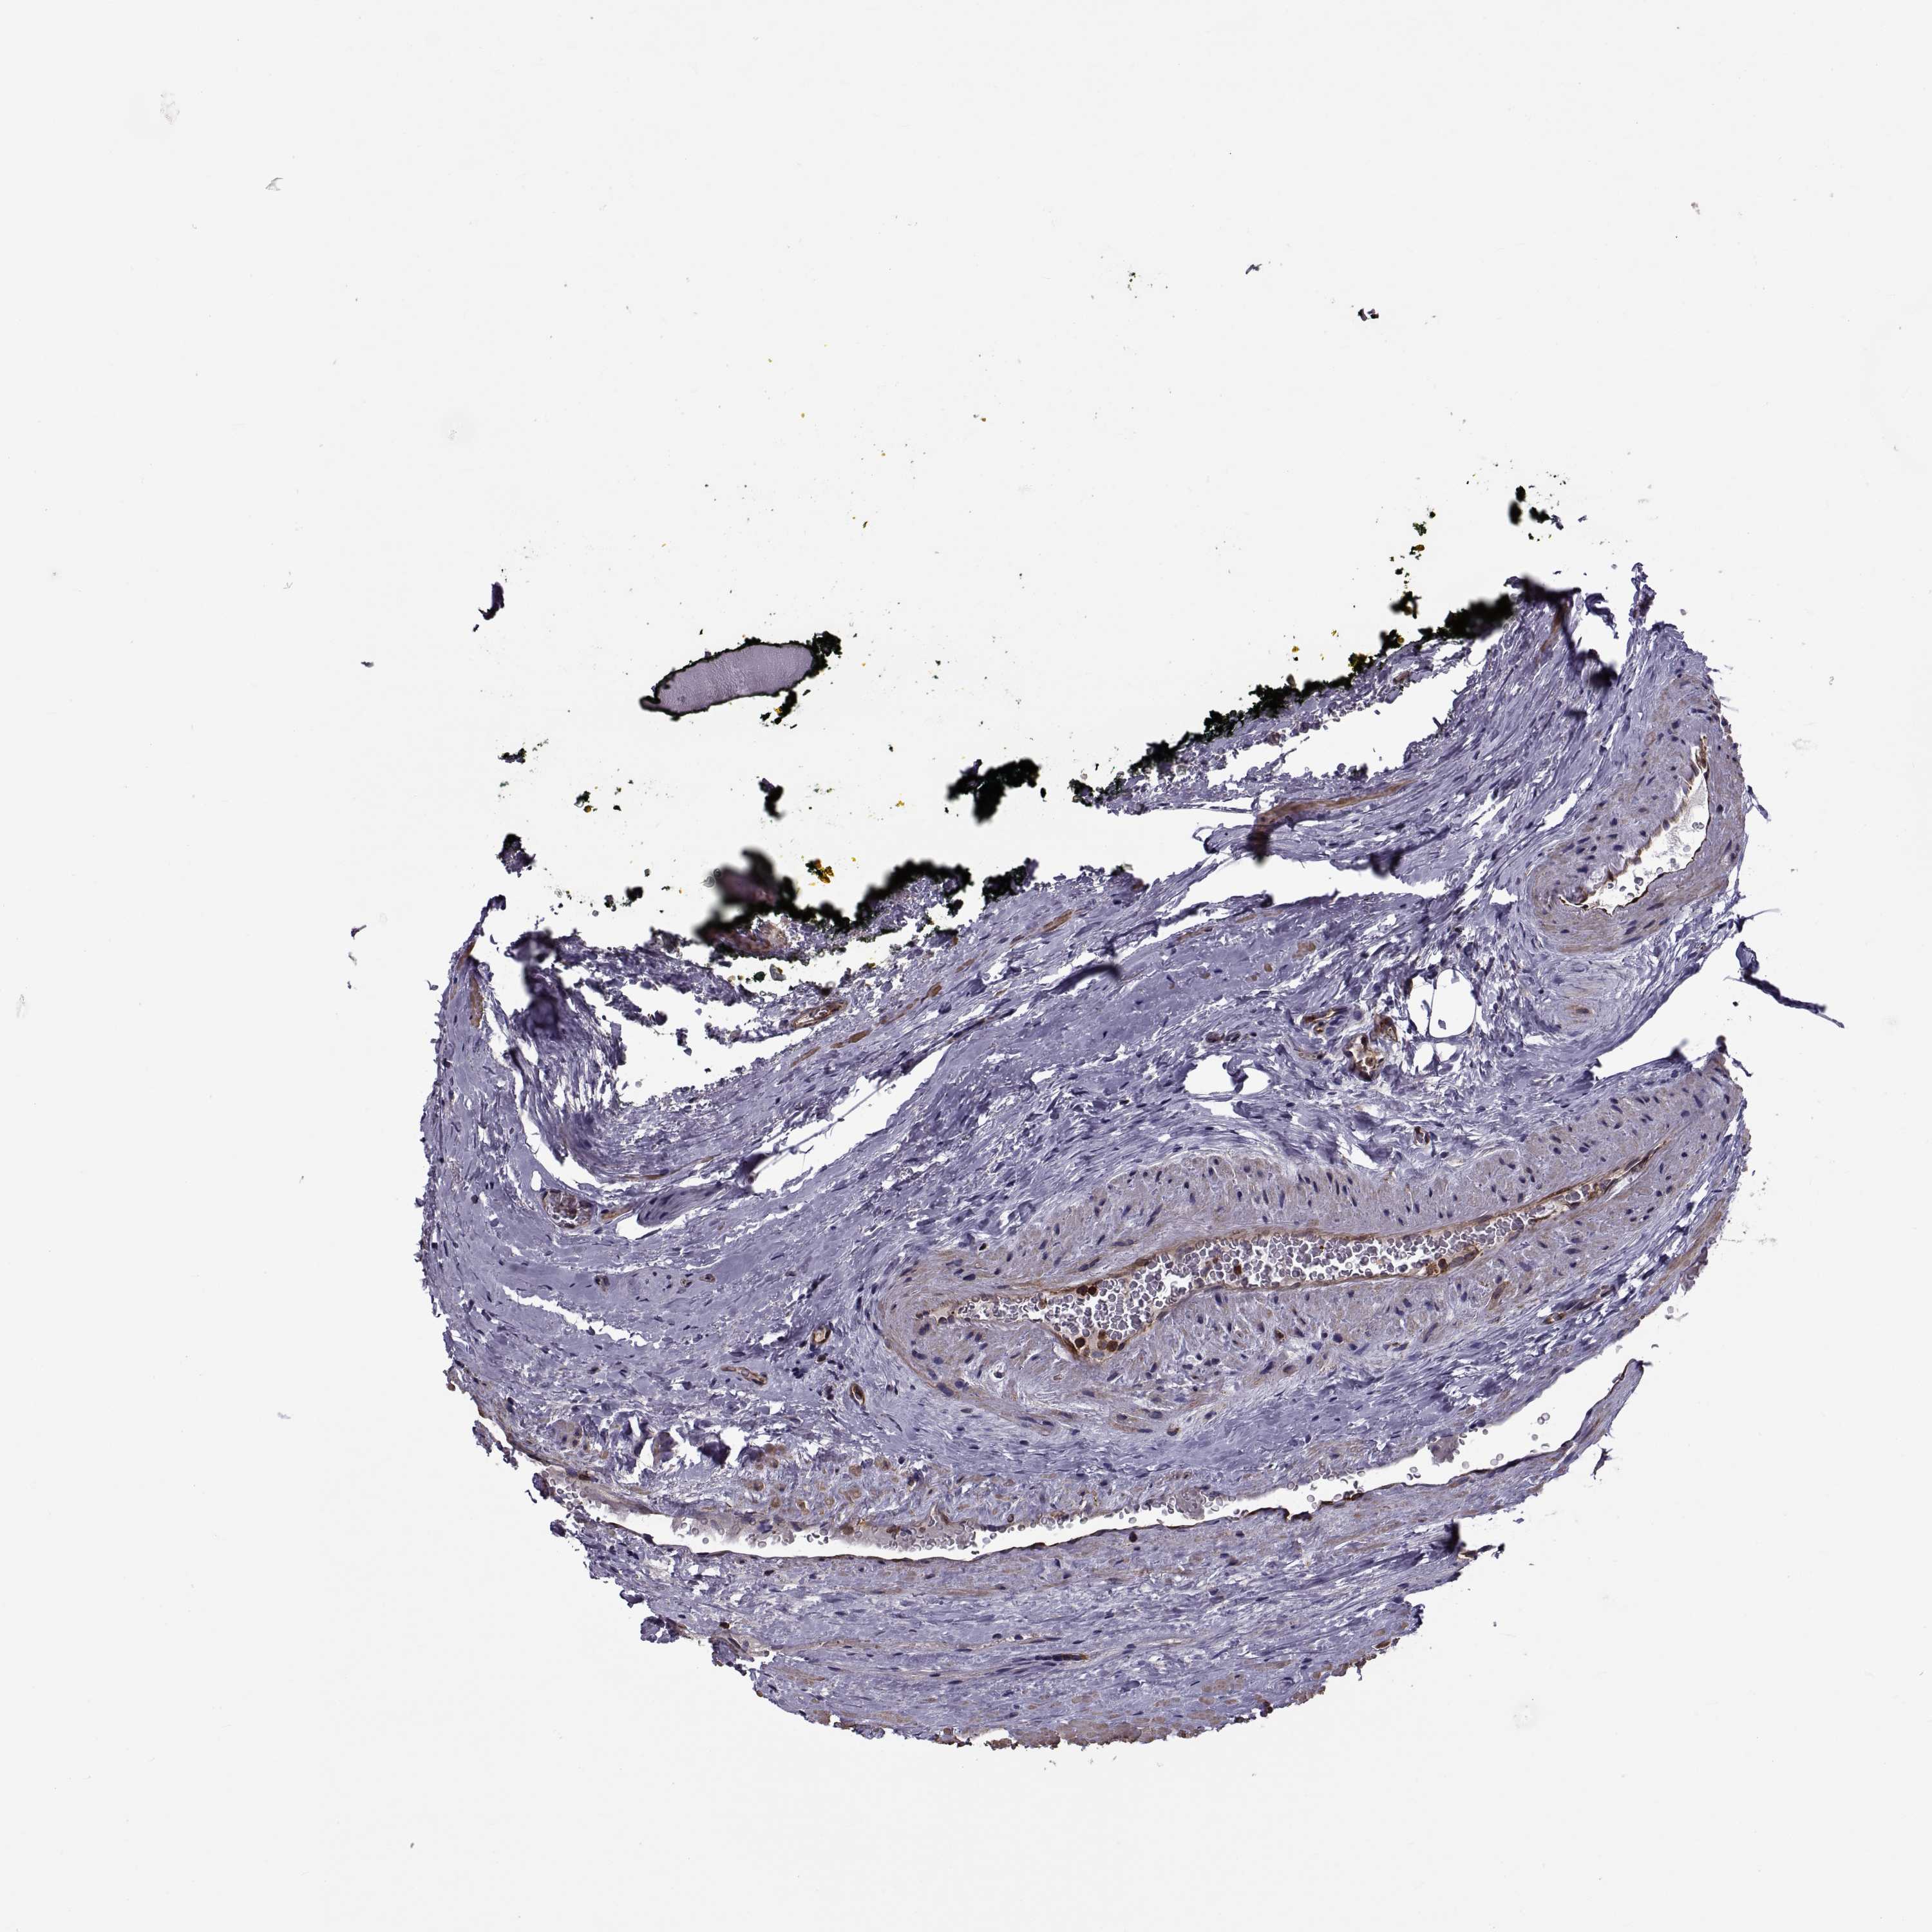

PROSTATE CANCER - Protein expressioni

A mouse-over function shows sample information and annotation data. Click on an image to view it in a full screen mode. Samples can be filtered based on level of antibody staining by selecting one or several of the following categories: high, medium, low and not detected. The assay and annotation is described here.

Antibody stainingi

Antibody staining in the annotated cell types in the current human tissue is reported as not detected, low, medium, or high, based on conventional immunohistochemistry profiling in selected tissues. This score is based on the combination of the staining intensity and fraction of stained cells.

Each image is clickable and will lead to virtual microscopy that enables deeper exploration of all samples and also displays staining intensity scores, fraction scores and subcellular localization as well as patient and tissue information for each sample.

Adenocarcinoma, Medium grade

Adenocarcinoma, NOS

Adenocarcinoma, High grade

Adenocarcinoma, Low grade